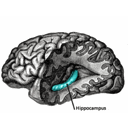

HippocampusAREA.png